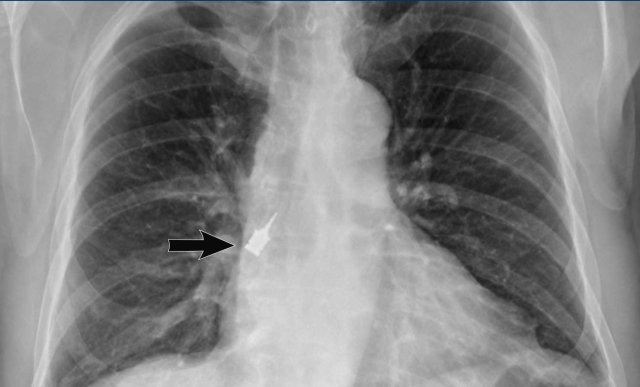

Image

Aspiration of device during dental surgery, visible in the right lower lobe bronchus.